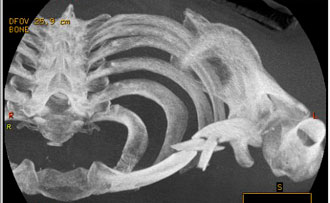

El doctor Ángel Villamor ha explicado en rueda de prensa que "nos ha costado bastante reconstruir la fractura debido a los muchos fragmentos en que estaba rota la clavícula". Villamor afirmó que "el pitón pasó entre el pulmón y la clavícula ,a pocos milímetros de la carótida o la yugular del cuello", añadiendo que la lesión que más preocupa es la cornada de la axila derecha. Cuestionado sobre los plazos de recuperación comentó: "Es complicado establecerlos pero en un mes podría estar listo".